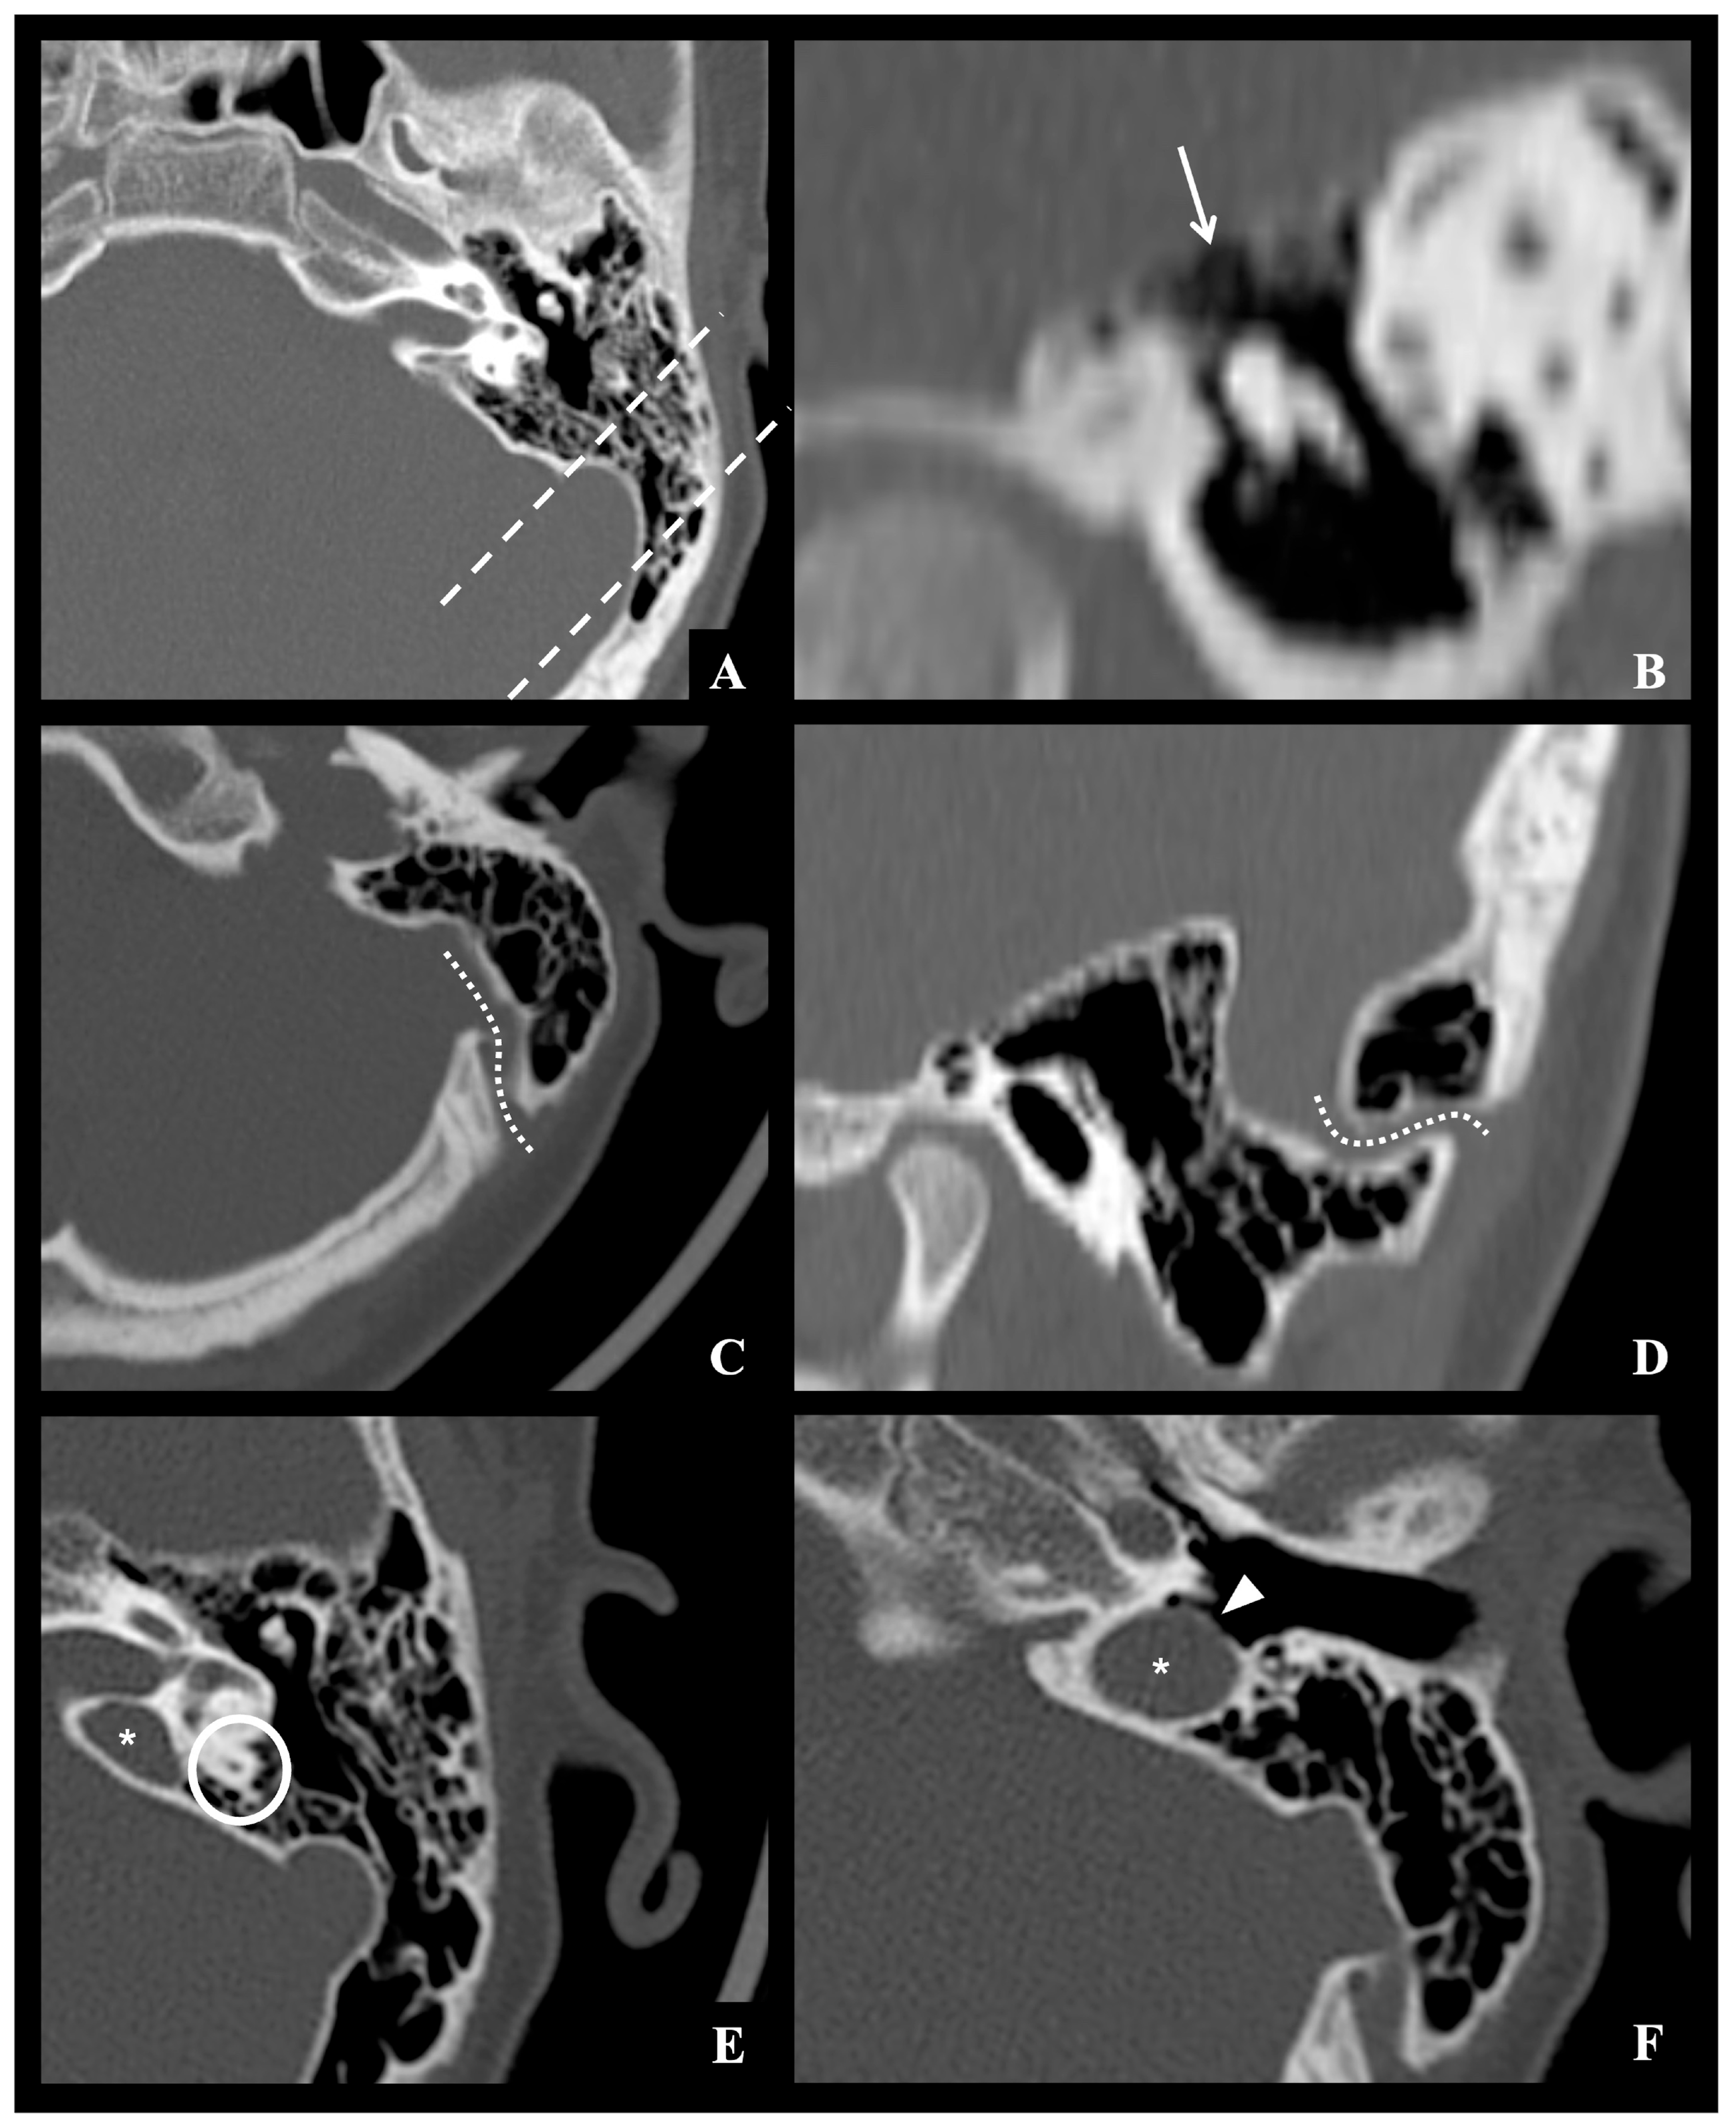

Acute otomastoiditis (AOM) is an infectious condition involving both the middle ear and the mastoid air cells, and it represents the most frequent secondary site of involvement in acute otitis media [1,2]. While most cases resolve without sequelae following appropriate antibiotic therapy, a small proportion may progress to complicated forms with extension of the infection to adjacent structures. These complications, which are broadly categorized as intracranial and extracranial, are associated with significantly increased morbidity, and require prompt recognition and management to prevent serious or permanent outcomes [3]. Intracranial complications, though relatively rare—with an estimated incidence ranging from 0.2% to 2%—are particularly severe and potentially life-threatening [4]. These include thrombosis of the transverse-sigmoid-jugular venous complex, meningitis, epidural empyema, subdural empyema, brain abscess, and in some cases secondary hydrocephalus [5]. An example of possible intracranial complications during AOM is shown in Figure 1.

Figure 1. MRI examples of the major possible otogenic intracranial complications in pediatric AOM patients: row (A) thrombosis of the transverse-sigmoid-jugular venous complex extending to superior sagittal sinus (white arrows) in a 13-year-old male patient with right-sided ACOM; row (B) right-sided ACOM in a 7-year-old female patient, with both extracranial extension (retromastoid abscess located beneath the proximal insertion of the sternocleidomastoid muscle—white arrowheads) and intracranial extension (epidural empyema of the posterior cranial fossa—white asterisks—associated with severe flow reduction in the transverse sinus—white arrows—and meningeal thickening); row (C) left-sided posterior cranial fossa subdural empyema (white dashed lines) in a 5-year-old male patient with large otomastoid abscess (black asterisks) and meningeal thickening; row (D) left middle cranial fossa brain abscess (white dotted circles) involving the temporal lobe secondary to ACOM in a 4-year-old female patient.